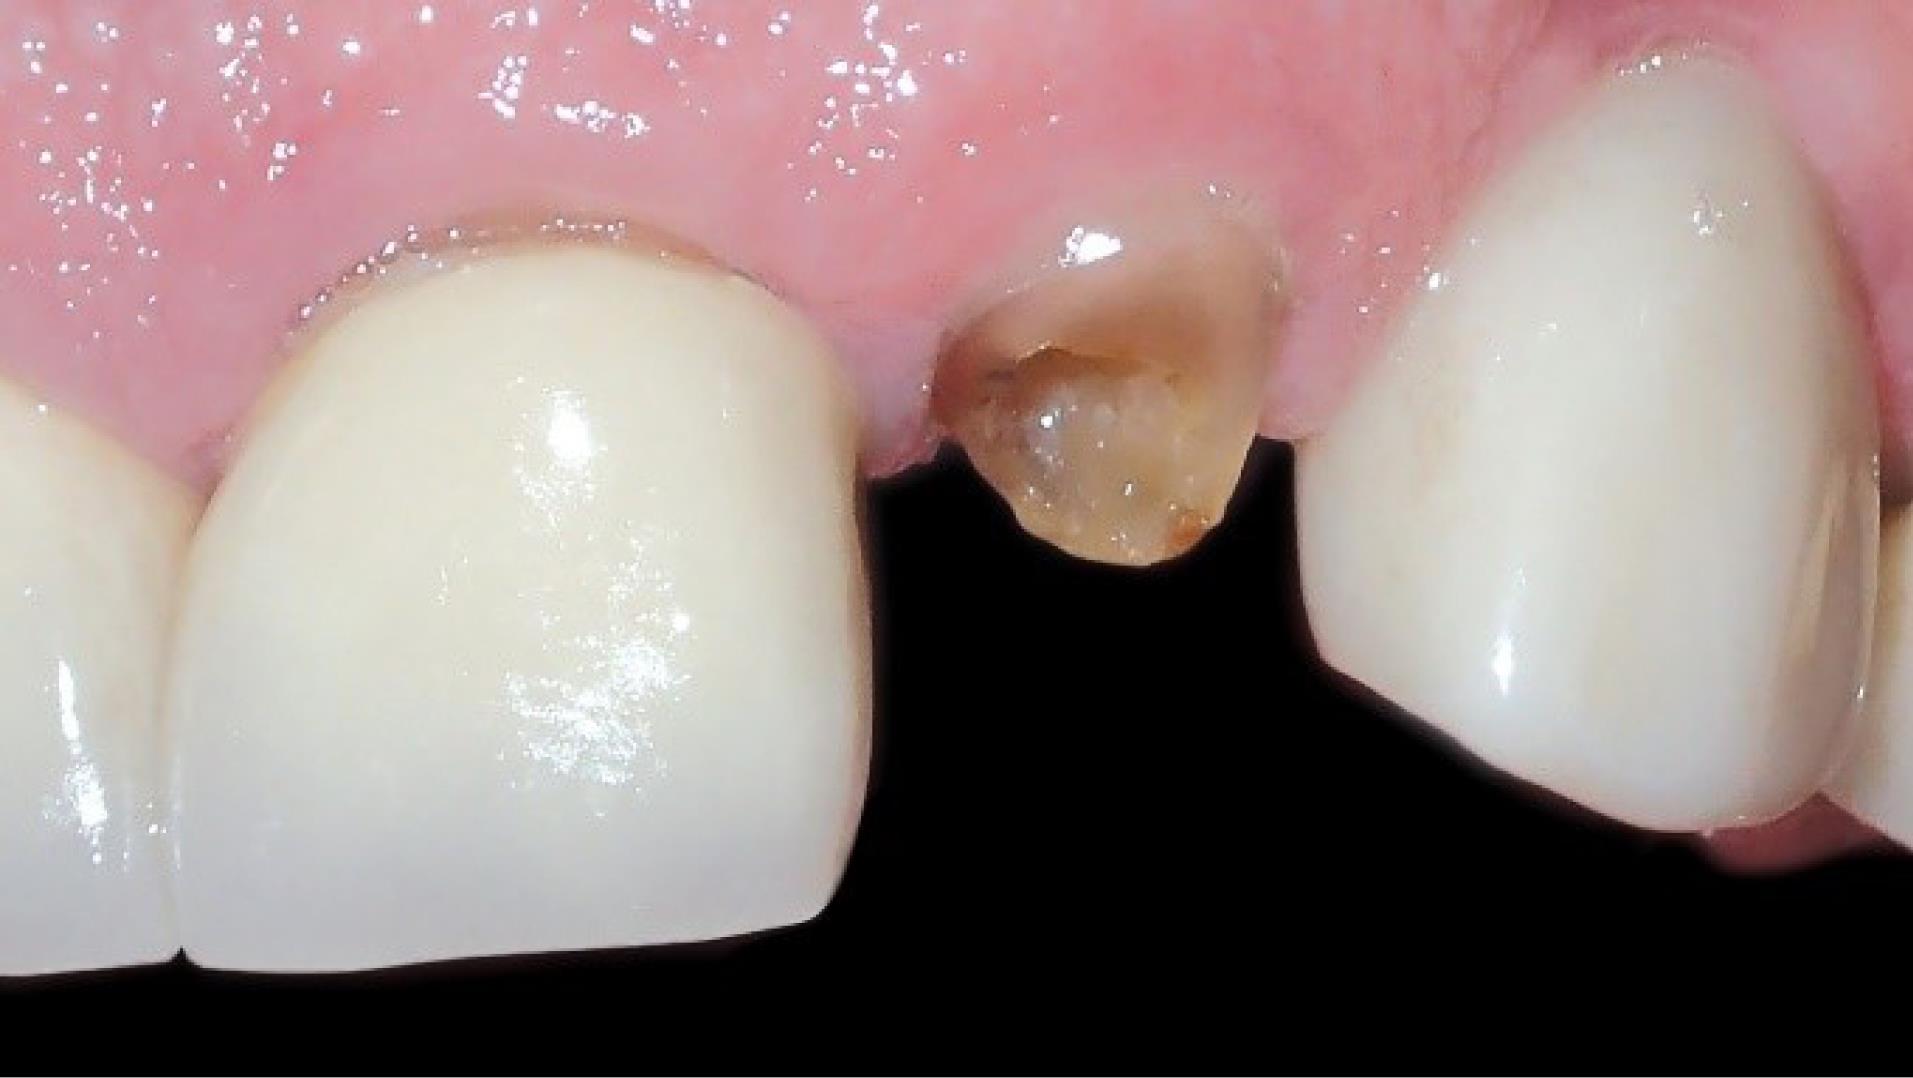

Figure 1.

Preoperative intraoral view